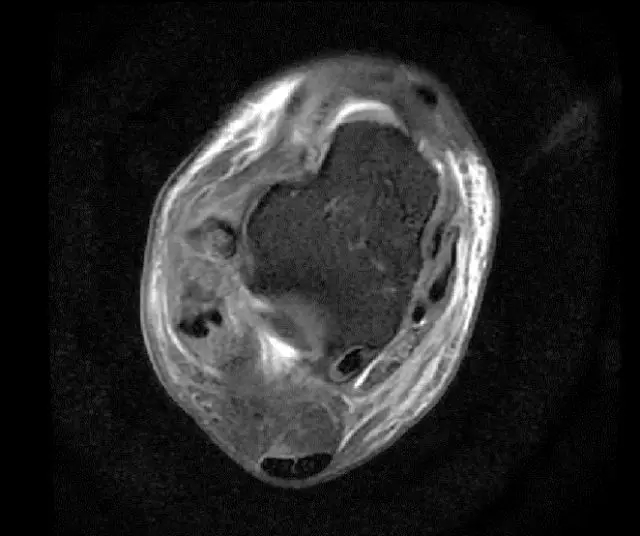

此片可以看到距腓前韧带和跟绯韧带有高信号大片的渗出病变,韧带结构松弛,增粗,这个地方可以看到腓骨前韧带的segond骨折块,所以考虑是踝关节外侧副韧带损伤,腓骨腱的segond骨折。